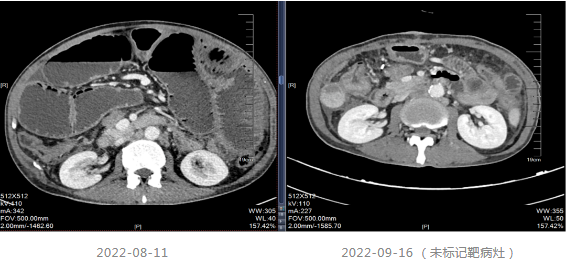

202-08出现肠梗阻,内科治疗效果不佳。

2022-08-29至武汉同济医院行小肠造瘘术。

▌四线治疗

患者出现肠梗阻,考虑病情PD,因此2022-10-06至今采用“斯鲁利单抗(200mg q3w)+呋喹替尼(4mg/d,口服,服3周停1周)”进行治疗,治疗过程中患者一般情况良好,体重增加。